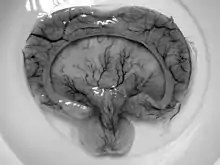

- Alobar holoprosencephaly

- Small single forebrain ventricle

- No interhemispheric division

- Absence of olfactory bulbs and tracts

- Absence of corpus callosum

- Non separation of deep gray nuclei[1]

- Semilobar holoprosencephaly

- Rudimentary cerebral lobes

- Incomplete interhemispheric division

- Absence or hypoplasia of olfactory bulbs and tracts

- Varying non separation of deep gray nuclei[1]

- Lobar holoprosencephaly

- Fully-developed cerebral lobes

- Distinct interhemispheric division

- Midline continuous frontal neocortex

- Absent, hypoplasic or normal corpus callosum

- Separation of deep gray nuclei[1]

- Syntelencephaly, or middle interhemispheric variant of holoprosencephaly (MIHV)

- Failure of separation of the posterior frontal and parietal lobes

- Callosal genu and splenium normally formed

- Hypothalamus and lentiform nuclei normally separated

- Heterotopic gray matter[1]